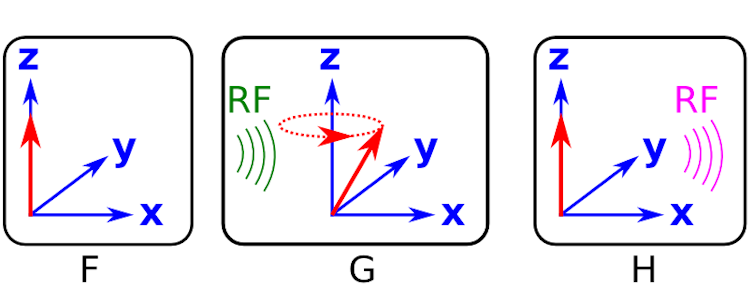

Figure F shows a cartoon of the excess of aligned protons (red arrows) in the patient. They appear as only a single red arrow because the dipole moment for each proton is sat on top of all the others.

Now, we need to “kick” the system. The way we do this is not with a bar magnet (as in figures B and C), but with a suitable radio frequency signal, approximately 60 MHz.

A radio frequency wave has both electric and magnetic fields. By generating a radio frequency wave and passing it through the body we disturb the protons, giving them energy. The protons have spin and so they precess around the z-axis (as opposed to just rocking back and forth like the compass needle).

An example of the protons precessing after the radio frequency wave has “kicked” the system is shown in figure G. The frequency of this precession is proportional to the strength of the magnetic field and is called the Larmor frequency. Again, in figure G, all of the protons are precessing at the same frequency and so the arrows are sat on top of one and other.

Up until now, all we have done is prepare the system by putting in energy in terms of electromagnetic fields - we haven’t actually measured anything. After the radio frequency pulse is applied, the precessing protons return to their equilibrium positions by emitting radio frequency waves (see figure H).

It is the magnetic field of this radio frequency wave - the magnetic resonance - that provides us with a signal that we can measure, and we do so with an induction coil.

Like we showed for the compass, the signal measured in magnetic resonance is also a damped sinusoidal wave that is caused by the dipole moments returning to their original orientations.

The signal shape is determined by the precession frequency and another effect called dephasing (see the second definition on this Wikipedia page). The dephasing causes the dipole moments of the protons to separate out rather than sitting on top of each other as is shown in figures F to H.